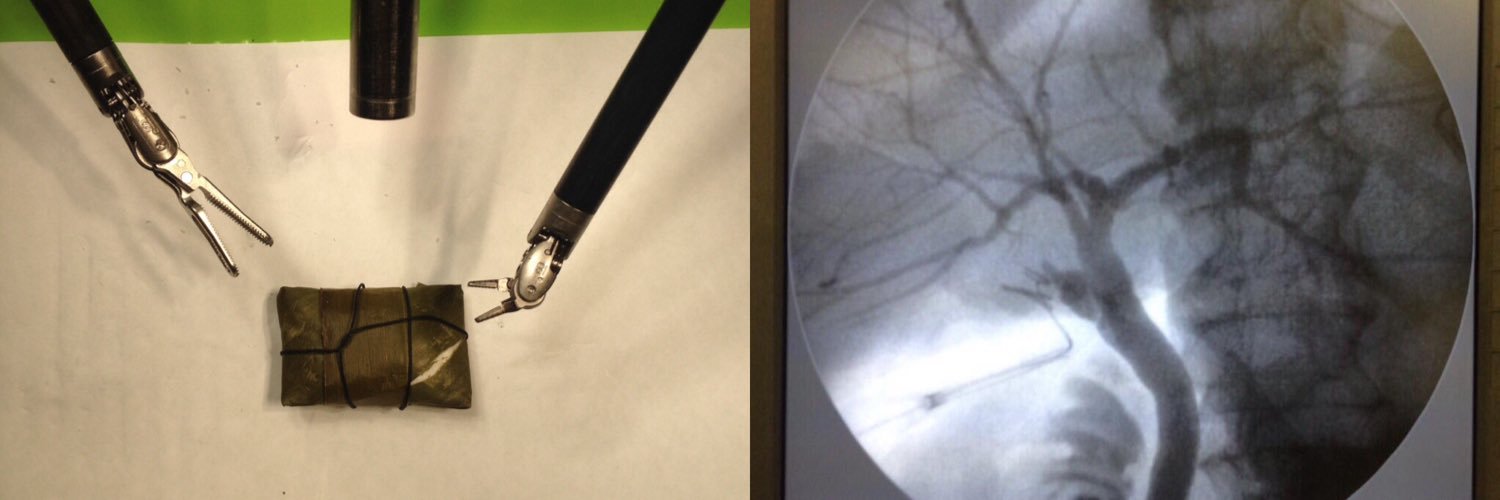

UVB HUCC3: Colelap+CIO en pte Post-CPRE fallida @liuma2000 @mafevisconti @CIMHUC @omaale7 @metalandros @drSanchezA